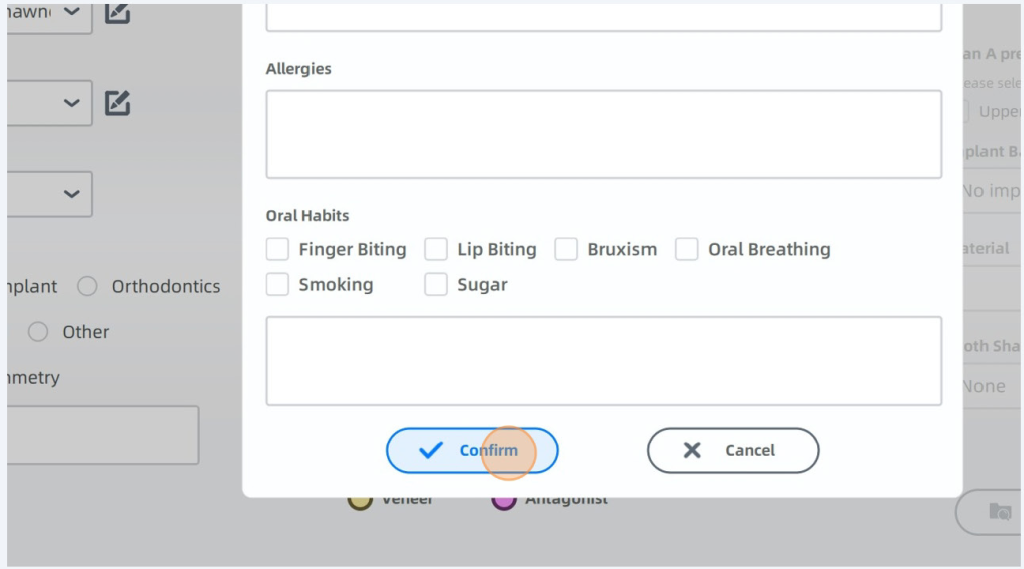

Enter Patients Name, Gender and Age required DOB optional

Click Confirm When Done